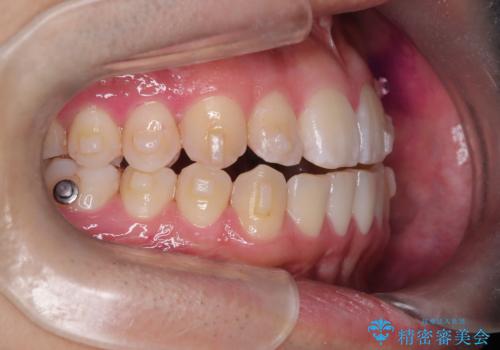

- 八重歯が気になるとのことでご来院されました。お口の中を確認すると、上の前歯がスペース不足で押し出され、少し前に出ている状態でした。抜歯せずに整えるため、奥歯を少しずつ後ろに動かしながら(遠心移動)、歯と歯の間をわずかに削るIPRを行ってスペースを作ることにしました。また、上下の噛み合わせを整えるために2級ゴム(エラスティック)を使用する方針を立てました。

マウスピースを段階的に交換しながら、奥歯を少しずつ後ろへ動かし、八重歯がきれいに並ぶよう調整しました。前歯の突出感を抑えるためにIPRを行い、スムーズに配列。さらに、2級ゴムを活用して噛み合わせも改善しました。治療後は、自然な歯並びになり、笑顔に自信が持てるようになったと喜んでいただきました。